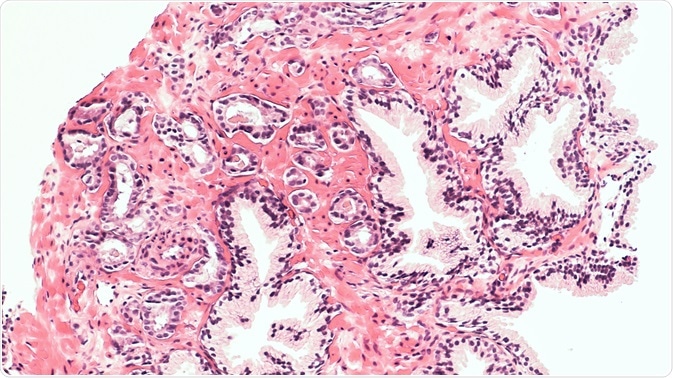

Shutterstock | David Litman

Prostate cancer TMAs were subjected to digital imaging and then the images were scored either visually or by digital analysis for ERβ2 staining in the tumor epithelium. The images for visual scoring were created by scanning the stained slides using an automated Tissuefax microscope (TissueGnostics, Tarzana, CA) and then were reviewed with the help of an online web gallery.